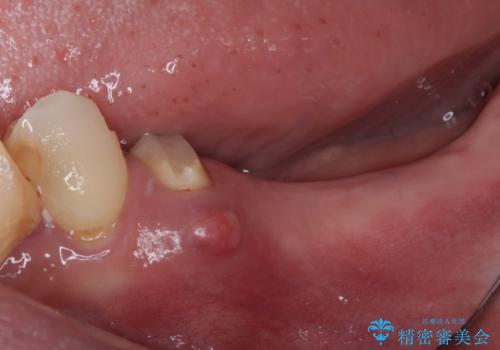

左下小臼歯は根管治療で対応する予定でしたが、診断のために歯肉を開いたところ頬側に垂直破折が認められたため、抜歯即時埋入インプラントによる補綴治療を選択することとしました。

右下は大臼歯部の歯は抜歯即時埋入インプラントにて、手前の歯は保存して補綴治療を行うこととしました。